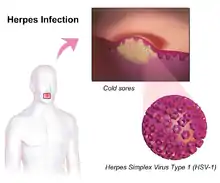

There are two types of herpes simplex virus, type 1 (HSV-1) and type 2 (HSV-2).[1] HSV-1 more commonly causes infections around the mouth while HSV-2 more commonly causes genital infections.[2] They are transmitted by direct contact with body fluids or lesions of an infected individual.[1] Transmission may still occur when symptoms are not present.[1] Genital herpes is classified as a sexually transmitted infection.[1] It may be spread to an infant during childbirth.[1] After infection, the viruses are transported along sensory nerves to the nerve cell bodies, where they reside lifelong.[2] Causes of recurrence may include: decreased immune function, stress, and sunlight exposure.[2][3] Oral and genital herpes is usually diagnosed based on the presenting symptoms.[2] The diagnosis may be confirmed by viral culture or detecting herpes DNA in fluid from blisters.[1] Testing the blood for antibodies against the virus can confirm a previous infection but will be negative in new infections.[1]

HSV infection causes several distinct medical disorders. Common infection of the skin or mucosa may affect the face and mouth (orofacial herpes), genitalia (genital herpes), or hands (herpetic whitlow). More serious disorders occur when the virus infects and damages the eye (herpes keratitis), or invades the central nervous system, damaging the brain (herpes encephalitis). People with immature or suppressed immune systems, such as newborns, transplant recipients, or people with AIDS, are prone to severe complications from HSV infections. HSV infection has also been associated with cognitive deficits of bipolar disorder,[15] and Alzheimer's disease, although this is often dependent on the genetics of the infected person.

| Herpes labialis | Commonly referred to as cold sores or fever blisters, herpes labialis is the most common presentation of recurrent HSV-1 infection following the re-emergence of the virus from the trigeminal nerve. |  |

- HSV-1 causes primarily mouth, throat, face, eye, and central nervous system infections.[4]